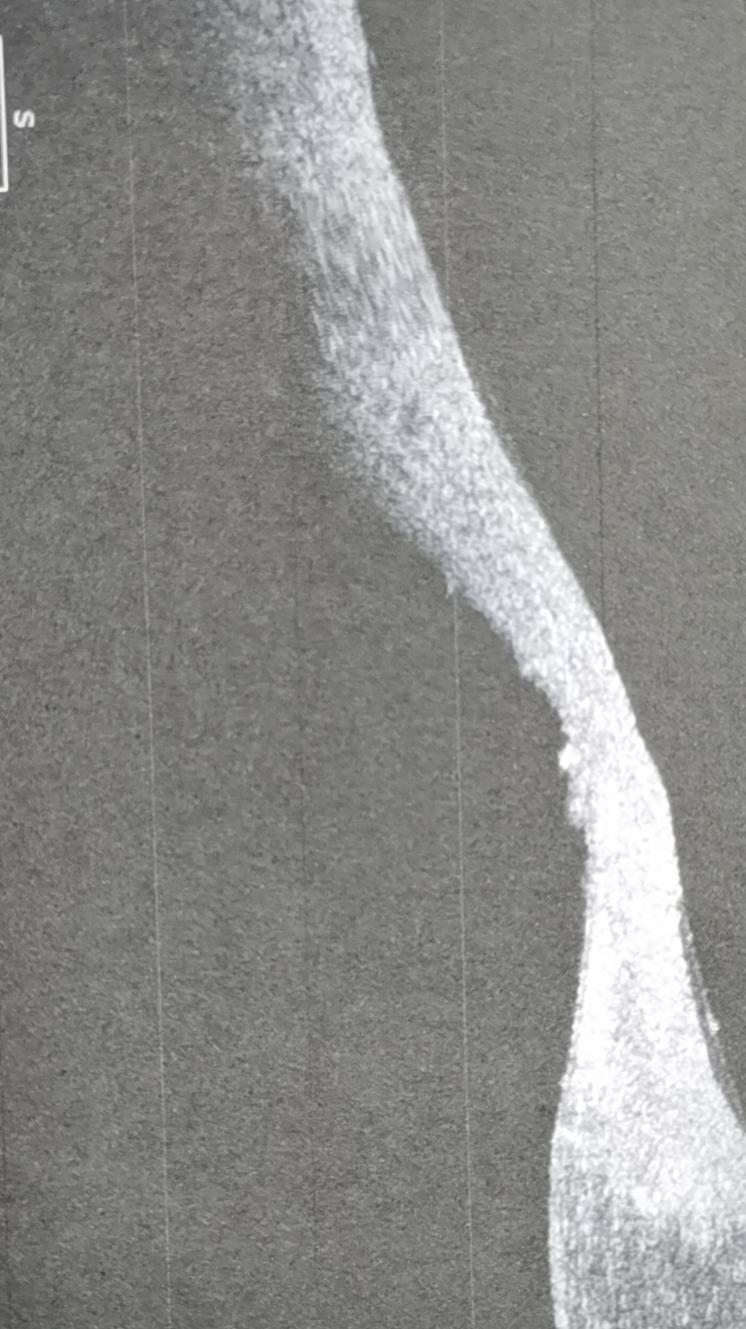

3月21日,我们仔细检查后发现老人双眼有严重的倒睫,并且因为睫毛长期刺激眼球,右眼形成了角膜溃疡,几乎穿孔......冲洗的过程中还发现睫毛根部有脓。老人觉得眼睛疼,主要原因就是倒睫和角膜溃疡引起的!另外老人左眼还有泪小管炎,右眼有慢性泪囊炎。

(Oct照片显示角膜溃疡,残余角膜厚度非常薄)